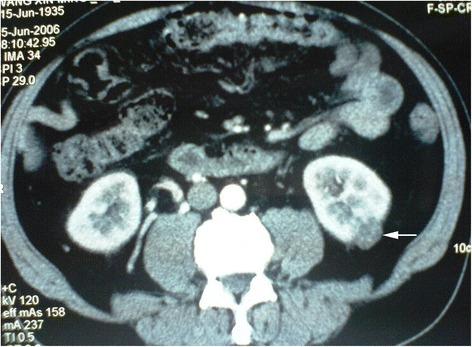

A total of 32 BSSRCC patients, including 28 males and 4 females, were enrolled the study from January 2004 to May 2016. The diagnoses were defined by the measurements of CT, ultrasound, and MRI. Patients with hereditary syndrome were excluded. The management of surgical manner, operation staging, and sequence were scheduled in accordance with the tumor's location and size (based on Zhongshan score, ZS score), as well as the performance status of the patients. Among them, 8 cases were conducted with bilateral surgical procedure simultaneously and 24 cases were implemented with staged operations. NSS on the one side with contralateral RN, and NSS on both sides were performed in 17 and 15 patients separately.

2004年1月至2016年5月,共纳入32例BSSRCC患者,其中男性28例,女性4例。通过CT、超声和MRI测量进行诊断。排除患有遗传性综合征的患者。根据肿瘤的位置和大小(基于中山评分,ZS评分)以及患者的体能状态安排手术方式、手术分期和顺序。其中,8例同时进行双侧手术,24例进行分期手术。17例患者行一侧保留肾单位手术(NSS)并对侧肾切除术(RN),15例患者行双侧NSS。